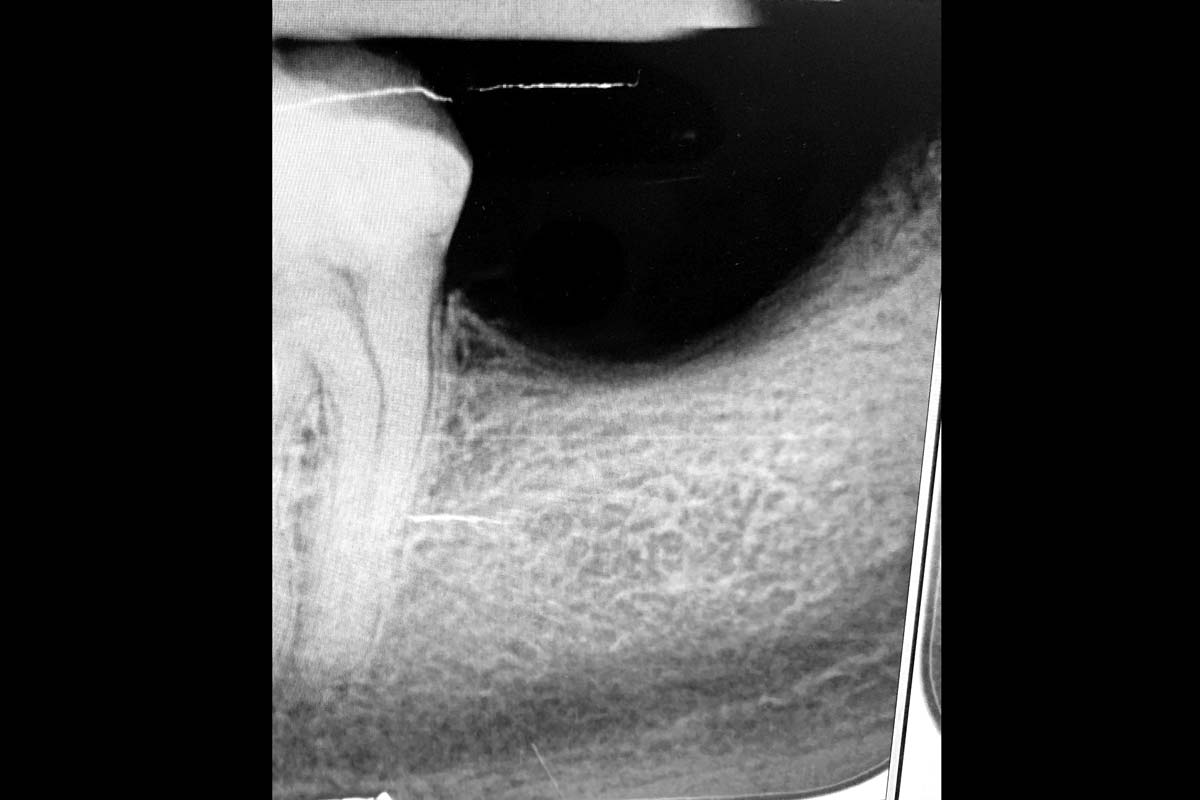

02/29 - Based on the intraoral x-ray a vertical bone defect of about 4 mm extending from 4.6 to 4.4 was determinedVertical bone augmentation and broadening of attached gingiva using cerabone®, permamem® and mucoderm® - Dr. R. Naimoli